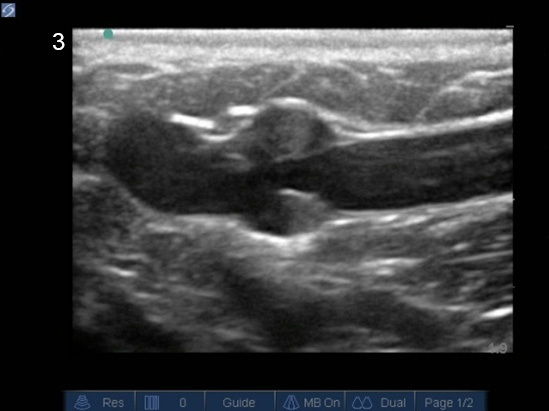

Gain Too Much Image